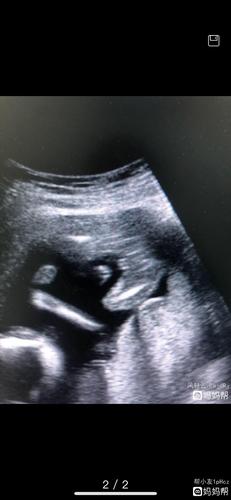

确认女宝b超图女孩,四维女孩脸图片 男女

刚做的b超,大家看看是不是女孩[求女宝]

15周b超女孩,看到三条线,确认是女宝

女宝b超三条白线图

女宝b超图典型的三线

女宝宝b超图片三条线

确认女宝B超图